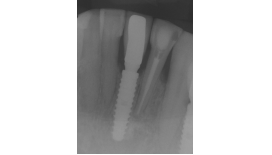

Na consulta seguinte, a coroa metalocerâmica foi instalada no elemento 41 e o orifício de acesso do parafuso foi restaurado com resina composta. Foi também realizada uma radiografia para posterior controle (Figuras 22, 23 e 24).

Após 12 meses, foi feita uma nova avaliação clínica e radiográfica, onde observou-se a boa manutenção dos tecidos peri-implantares (Figuras 25 e 26).